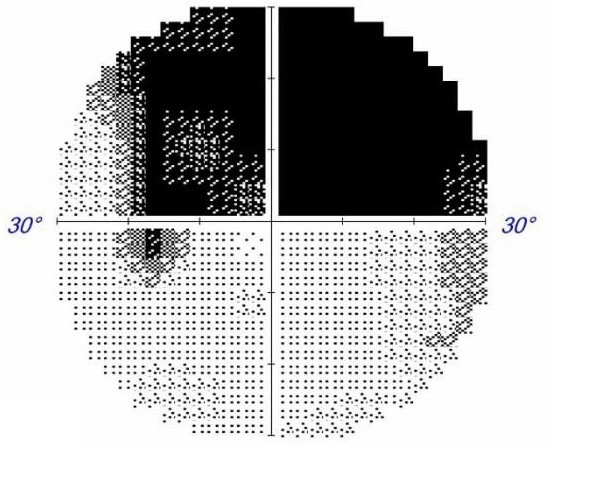

執業於台南的青光眼專科醫師林柏安提醒,絕大部分青光眼患者早期並沒有症狀,但青光眼會逐漸傷害視神經,最終導致失明。他強調,正確診斷與及早治療是預防視力受損的關鍵。

林柏安醫師指出,青光眼的高危險群包括40歲以上、家族遺傳史、高度近視或是高度遠視、糖尿病、低血壓、長期使用類固醇、眼睛有外傷等。林醫師特別強調,測量眼壓只是青光眼檢查的諸多項目之一,不能光憑「高眼壓」來診斷青光眼,尤其亞洲地區好發「正常眼壓型青光眼」,眼壓數值雖正常,卻已出現視神經傷害及視野缺損。若有疑似青光眼,需要接受眼科醫師詳細及全面的檢查。檢查建議包括以下項目:

- 視野檢查